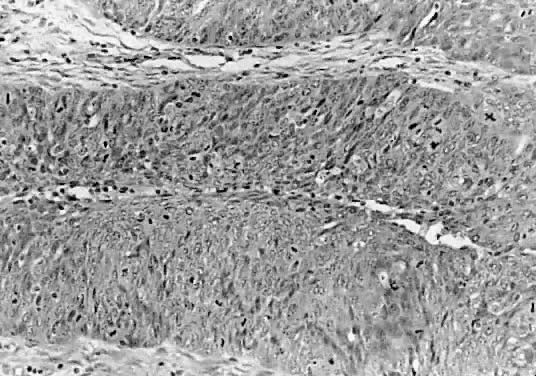

Epithelial cells devoid of connective tissue detach, fall, and form rosette-like structures that float in the cystic fluid; this phenomenon is designated as tufting (Figs. 7 and 8). Hyalinization of the connective tissue of the papillary structures is seen more often in the LMP serous tumors than in serous cystadenomas.19 Papillae undergoing ischemic changes show edema and frequently slight acute inflammation of the stroma. In more advanced cases, frank necrosis may be evident.

Fig. 8. Serous cystadenoma of low malignant potential demonstrating papillae, stratification of epithelial lining, tufting, stromal edema with hyalinization, and focal acute inflammatory cell infiltrate. On the upper right-hand corner, a psammoma body is clearly seen (hematoxylin and eosin, 420).